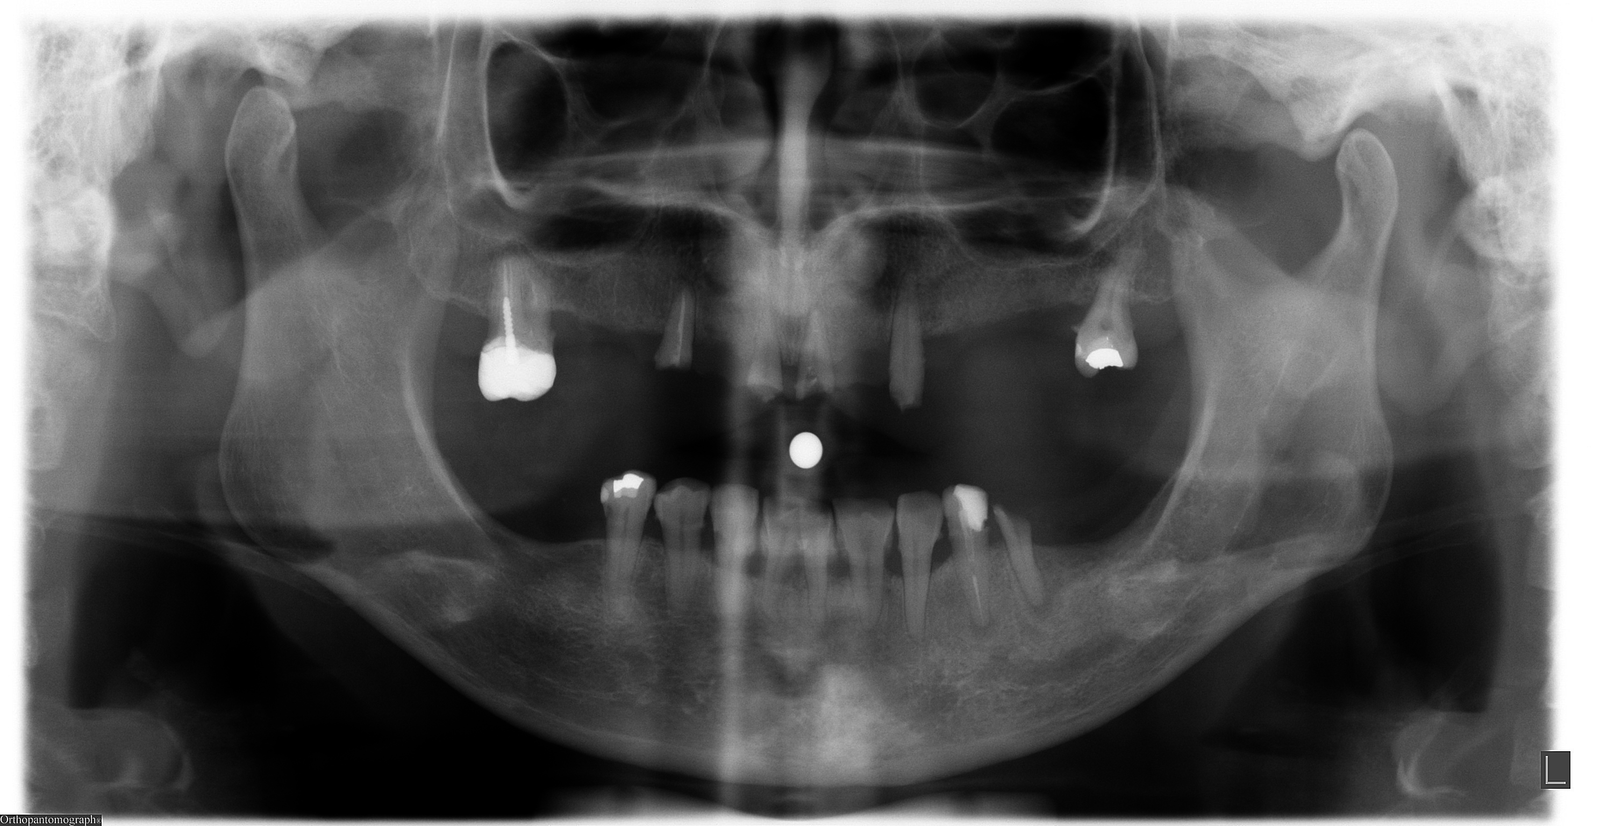

Hola a todos, Voy a realizar una cirugía regenerativa en el implante del 46 , no se que implante es y necesito saberlo para localizar el tornillo de cierre, su [...]

Hola! Me llega a la clínica este paciente sin ningun tipo de información sobre los implantes que lleva, con los pilares puestos y sin las coronas porque las ha perdido. [...]

Hola. Esta paciente acude a mi consulta para recibir tratamiento. Los implantes mandibulares sé que son Avinent hexágono externo de diámetro 3.8 y compatibles con hexágono tipo Bränemark universal, sin [...]

Buenas. Me gustaría saber si alguien reconoce estos implantes. Son de hexágono externo y llevan multiunit. Es una paciente de iDental. Muchas gracias Un saludo

paciente llega a consulta con implantes desconocidos, al laboratorio nos llega fotos de radiografía

Podrían ayudarme con estos implantes. Fueron colocados en Madrid hace aprox 6 años para una sobredentadura con locator. Muchisimas gracias

Paciente que viene para nueva rehabilitación superior, necesitaria saber qué tipo de implante son estos dos que os mando en la foto y radiografía, pues me interesaria usarlos en la [...]

Hola compañeros me ha llegado este caso de idental y por supuesto no tiene nada que haga referncia a sus implantes parece que tiene dos tipos diferentes en el segundo [...]